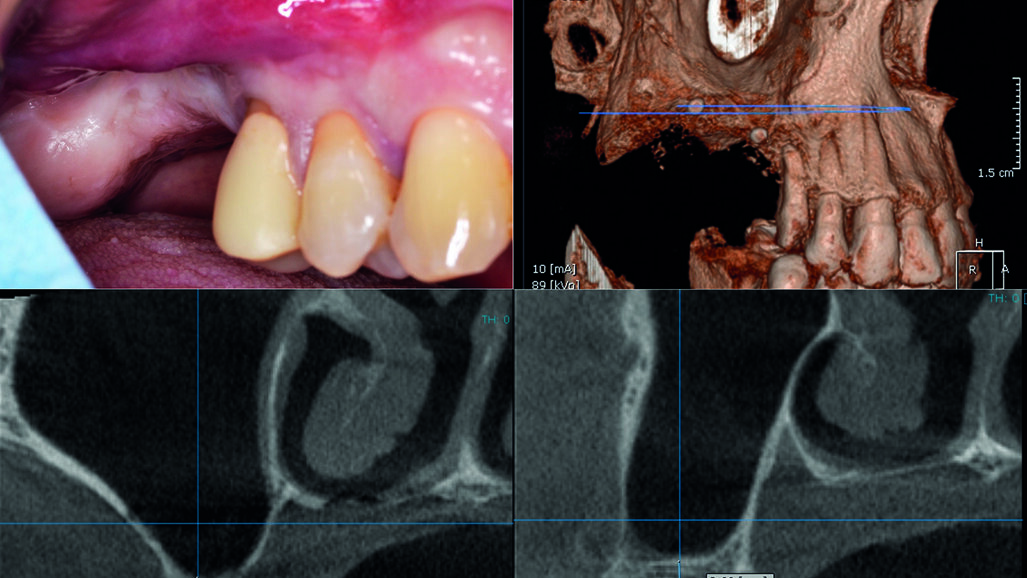

Il paziente (A/M, 60 anni) presentava una marcata atrofia verticale a carico dell’arcata superiore destra in posizione 1.6 e 1.7 (Fig. 1). Un’attenta valutazione del caso portava ad escludere l’opportunità di eseguire un intervento di rigenerazione ossea guidata (GBR) in senso verticale; il paziente infatti presentava un fornice quasi totalmente assente, i piani anatomici completamente sovvertiti per pregressi interventi chirurgici nel primo quadrante, una limitata apertura orale e, in aggiunta, una scarsa compliance. Al paziente è stato quindi proposto un piano di riabilitazione impianto-protesica basato sull’inserimento di due impianti in associazione ad una tecnica idropneumatica di rialzo del seno mascellare per via crestale su siti multipli, eseguito attraverso l’innesto della pasta ossea precedentemente descritta.

L’area di intervento è stata anestetizzata utilizzando articaina cloridrato 40 mg con adrenalina 1:100000. Si è proceduto quindi a sollevare un lembo trapezoidale a tutto spessore mediante un’incisione crestale anticipata palatalmente. Dopo avere posizionato una dima radiologica, appositamente fabbricata, si è proceduto a marcare i siti implantari sulla corticale ossea in corrispondenza dei reperi metallici, e a preparare i tunnel implantari per mezzo del sistema “Crestal Approach Sinus Kit” (BetaPharm, Via Brigata Berto 10 - 16030 Cogorno - Italia). Da notare che l’altezza ossea residua (Residual Bone Height o RBH) inferiormente al seno mascellare variava tra i 3,66 mm e i 2,84 mm.

Fig. 1 - Aspetto clinico e radiografico dell’arcata superiore destra del paziente alla prima visita. La zona corrispondente agli elementi 1.6 e 1.7 presente una grave atrofia ossea verticale.